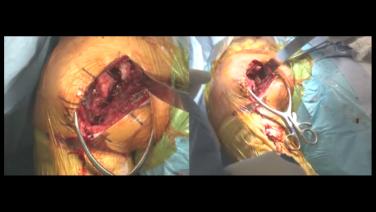

Acute Full Thickness Rotator Cuff Tear - Surgical Demonstration - Stephanie Muh, MD